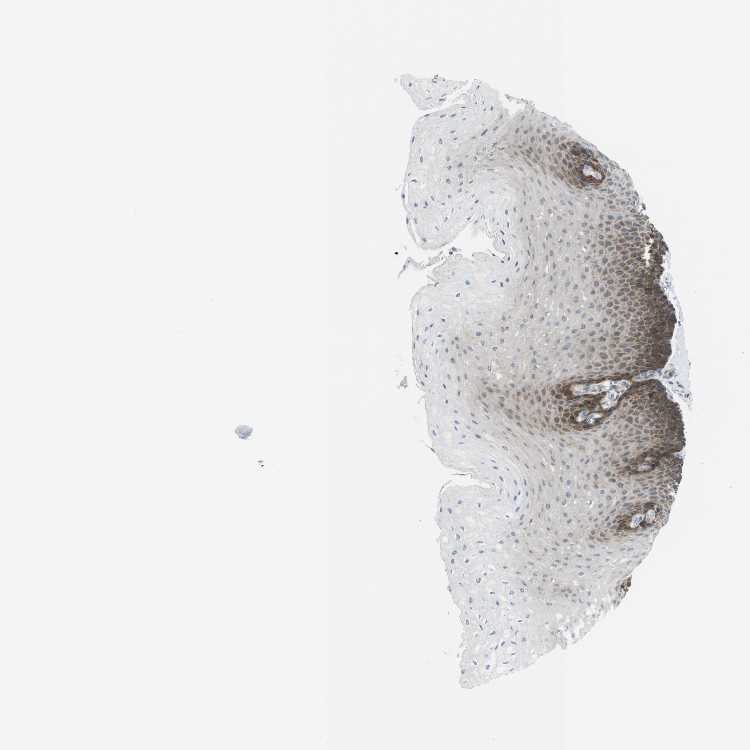

ESOPHAGUS - Antibody stainingi

Antibody staining in the annotated cell types in the current human tissue is reported as not detected, low, medium, or high, based on conventional immunohistochemistry profiling in selected tissues. This score is based on the combination of the staining intensity and fraction of stained cells.

Each image is clickable and will lead to virtual microscopy that enables deeper exploration of all samples and also displays staining intensity scores, fraction scores and subcellular localization as well as patient and tissue information for each sample.

Antibody HPA015006Antibody HPA029040Antibody HPA029041Antibody HPA050052

Squamous epithelial cells HighHighLowMedium